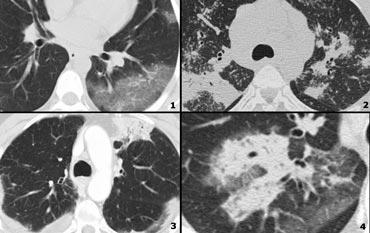

Low Attenuation pattern

- Bệnh u cơ bạch mạch (LAM): các nang đồng đều ở phụ nữ trong độ tuổi sinh đẻ; không có tiền sử hút thuốc; hạch to và tràn dịch màng phổi; đôi khi tràn khí màng phổi.

- LCH: nhiều nang hình tròn và hình dạng bất thường; tiền sử hút thuốc lá.

- Honeycombing

- Khí phế thũng trung tiểu thùy: vùng giảm đậm độ không có thành.

Low Attenuation pattern (2)

- Khí phế thũng trung tiểu thùy: các vùng giảm đậm độ không có thành. Lưu ý động mạch trung tiểu thùy ở trung tâm.

- Mô bào tế bào Langerhans (LCH): nhiều nang thành dày; tiền sử hút thuốc lá.

- Honeycombing.

- Bệnh u cơ bạch mạch (LAM): các nang đều đặn ở phụ nữ trong độ tuổi sinh đẻ.